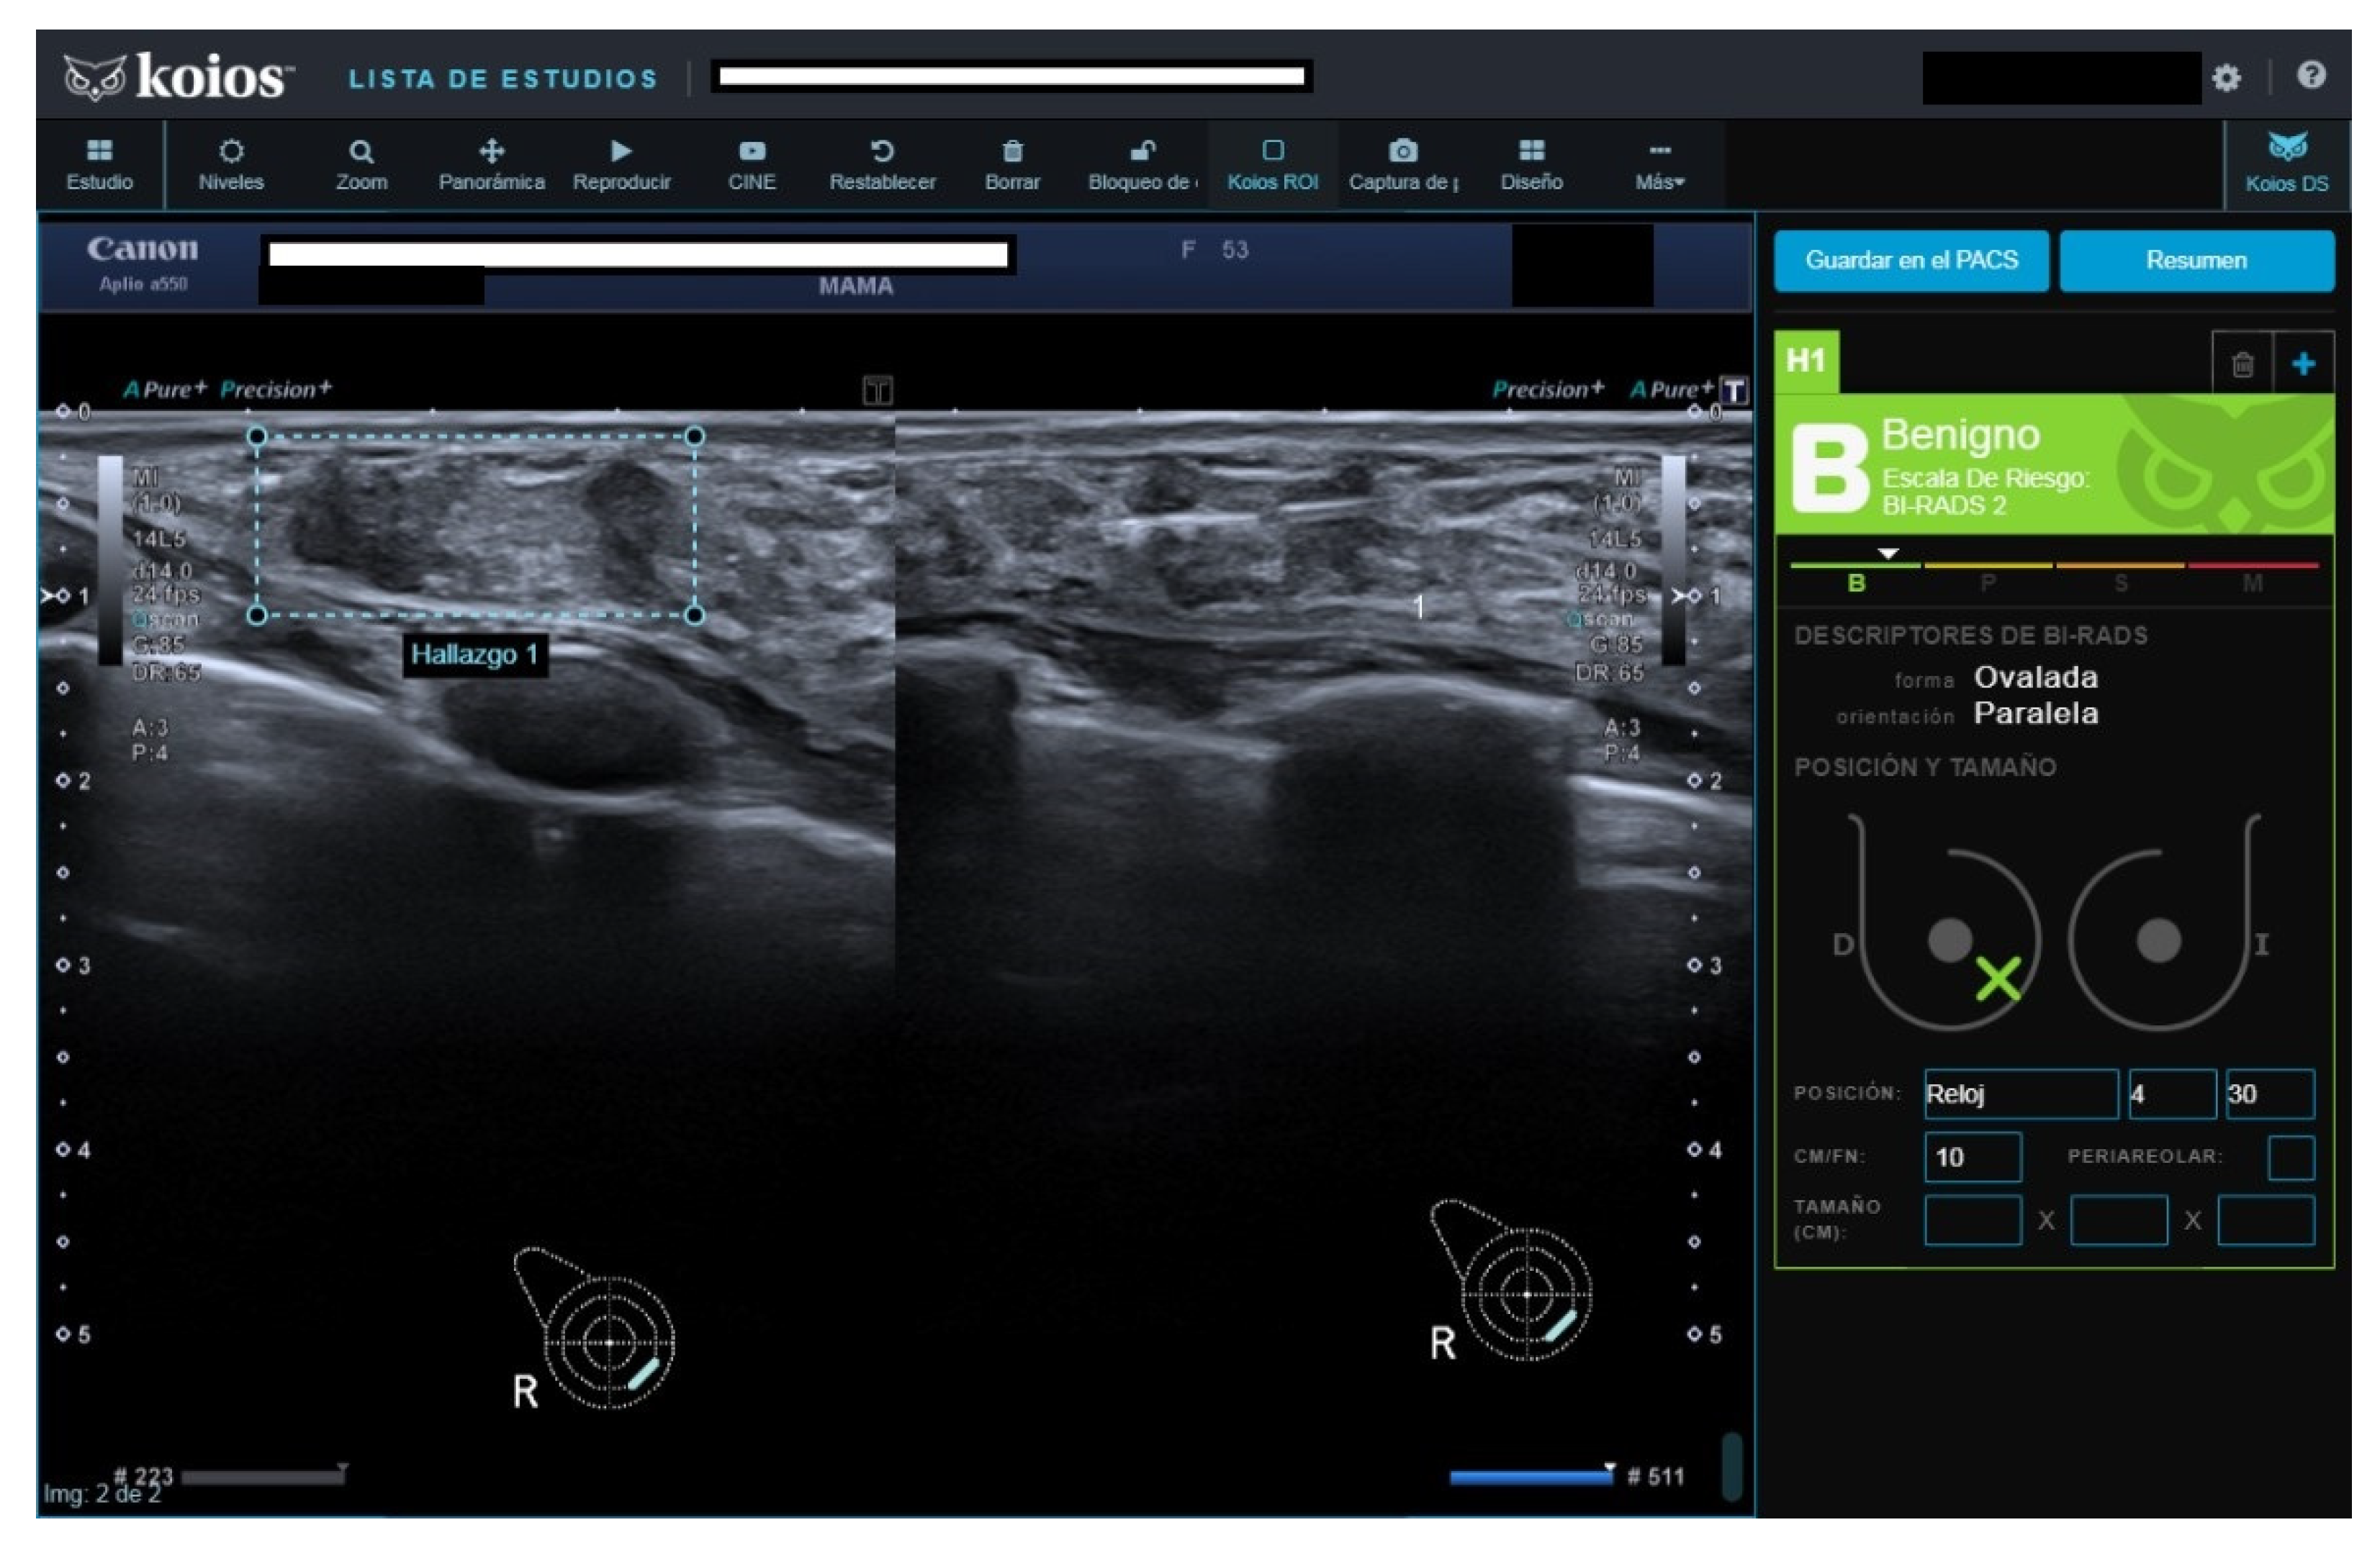

Figure 3.

Nodule rated B3 by reader, Kpb by KOIOS. Cytology reported fibroadenoma with simple hyperplasia; biopsy rendered a fibroadenoma diagnosis.